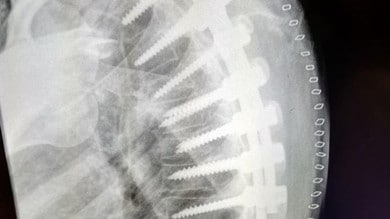

L’esame radiografico della colonna vertebrale completa (in toto) è un esame radiologico condotto mediante l’utilizzo di raggi X che riescono ad attraversare il corpo umano e a imprimersi in modo fotograficoIl risultato è un’immagine che evidenzia in modo differente ossa e scheletro rispetto ai tessuti molli (muscoli e pelle. Ho un problema alla schiena,una ernia L4L5 e responsabile di compressione sull’emergenza radicolare di L5 bilaterale Mi hanno mandato a fare un po’ di ciclo di ginnastica posturale e rinforzo della muscolatura addominale e anche di dimagrire,ma io al camminare sento un dolore fortissimo dalla coscia fino alla caviglia. Come Determinare se Hai la Polmonite La polmonite è un'infezione che si sviluppa nelle sacche d'aria all'interno dei polmoni Può essere causata da batteri, virus o funghi che iniziano a moltiplicarsi Questa malattia è più pericolosa per.

Lastra alla schiena. È bene rammentare che con la radiografia della colonna lombosacrale non si possono fare diagnosi di ernia del disco, ma solo escludere altre malattie con sintomi simili (tumori, forme infiammatorie, fratture, malformazioni ecc) La TAC e la RM sono pressoché sovrapponibili in termini di valore diagnostico per il medico;. Devo fare la lastra alla schiena!?. Ormai la schiena e il sedere mi fanno abbastanza male e ho solo 17 anni Grazie a tutti.